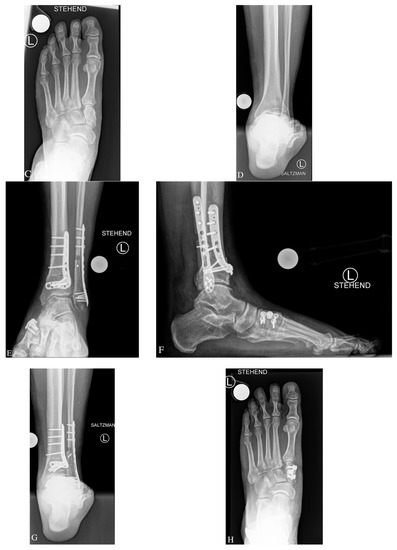

3.2. Preoperative Radiological Angle Measurements